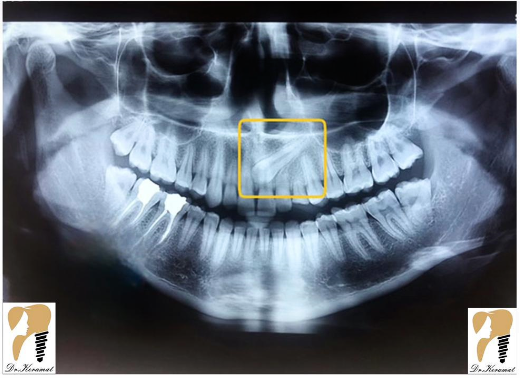

برای تشخیص نهفتگی دندان متخصص شما را به انجام عکسبرداری و رادیوگرافی ارجاع می دهد. یک رادیوگرافی OPG حتما مورد نیاز است. در بعضی موارد برای تشخیص دقیق محل دندان نیاز به رادیوگرافی تکمیلی از جمله رادیوگرافی اکلوزال, لترال سفالومتری و یا CBCT می باشد.

اگر رادیوگرافی OPG تهیه کردید و با چنین تصویری مواجه شدید حتما از یک متخصص جراح فک و صورت کمک بگیرید.